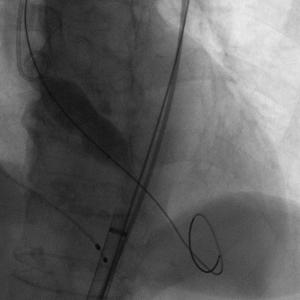

患者插管后已可以耐受造影剂,常规左侧作为辅入路进行操作,翻山造影后进行穿刺等操作,患者辅入路植入猪尾造影,根据造影调整体位使无窦,右窦,左窦分离,右窦居中,三个窦保持在同一平面,之后常规跨瓣进行后续操作。

主动脉根部造影

Numed18球囊扩张